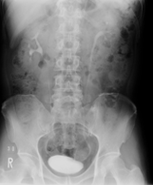

DIP(点滴静脈性腎盂造影)とは

造影剤を点滴静注し、腎臓、尿管、膀胱の形態的変化を10分・20分・30分で撮影し尿管の閉塞などが明瞭になります。

10分 20分 30分

また、膀胱像の大きさ(萎縮)、肉柱形成(神経因性膀胱)、偏位(周囲からの圧迫)、陰影欠損(腫瘍、尿管癌)などについて観察します。